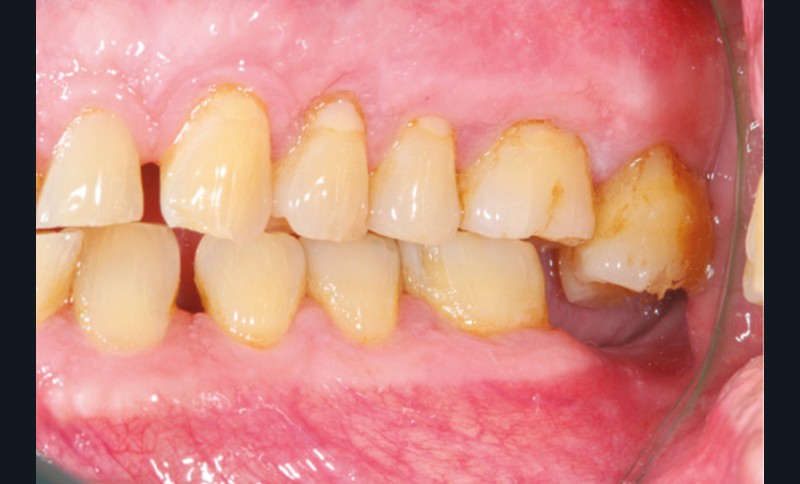

Le principe de protection mutuelle implique que les dents postérieures protègent les antérieures lors de la mastication. Des extractions non compensées de molaires, par exemple, entraîneront une hypersollicitation des antérieures et une usure importante du fait du principe de calage ainsi qu’un risque de perte de dimension verticale (fig. 10 à 13).